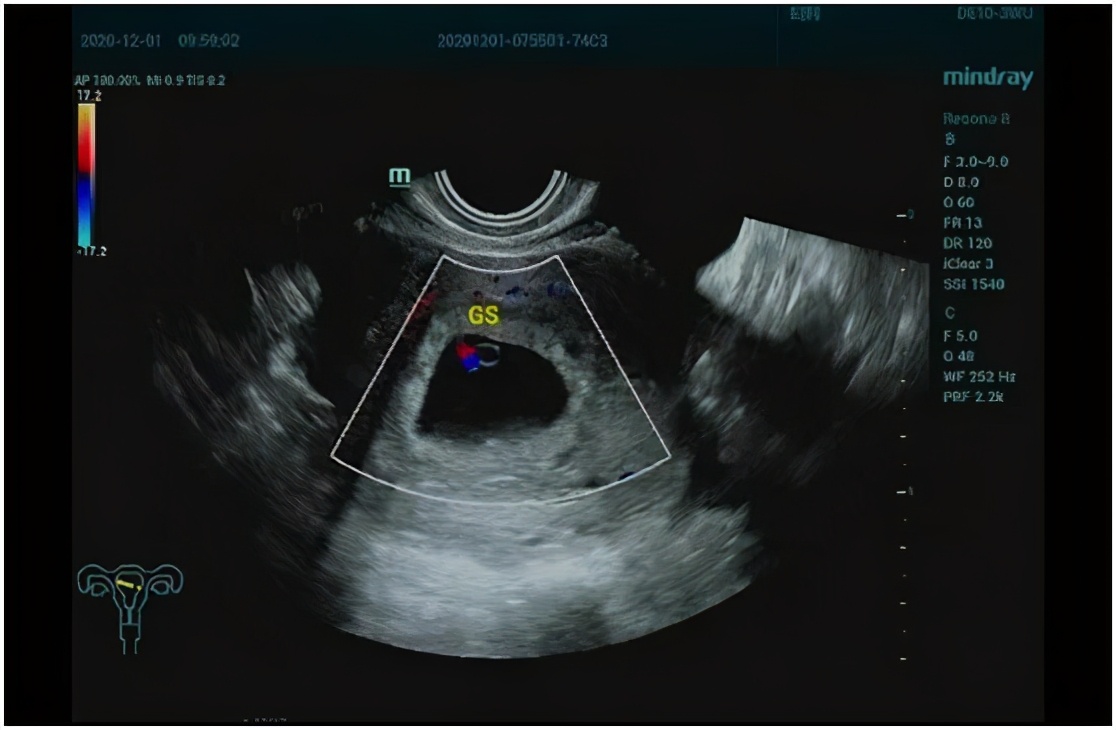

现在生命已经开始萌芽,B超都能看到小小的胚芽和鲜活的胎心,幸福真真切切地摆在眼前!